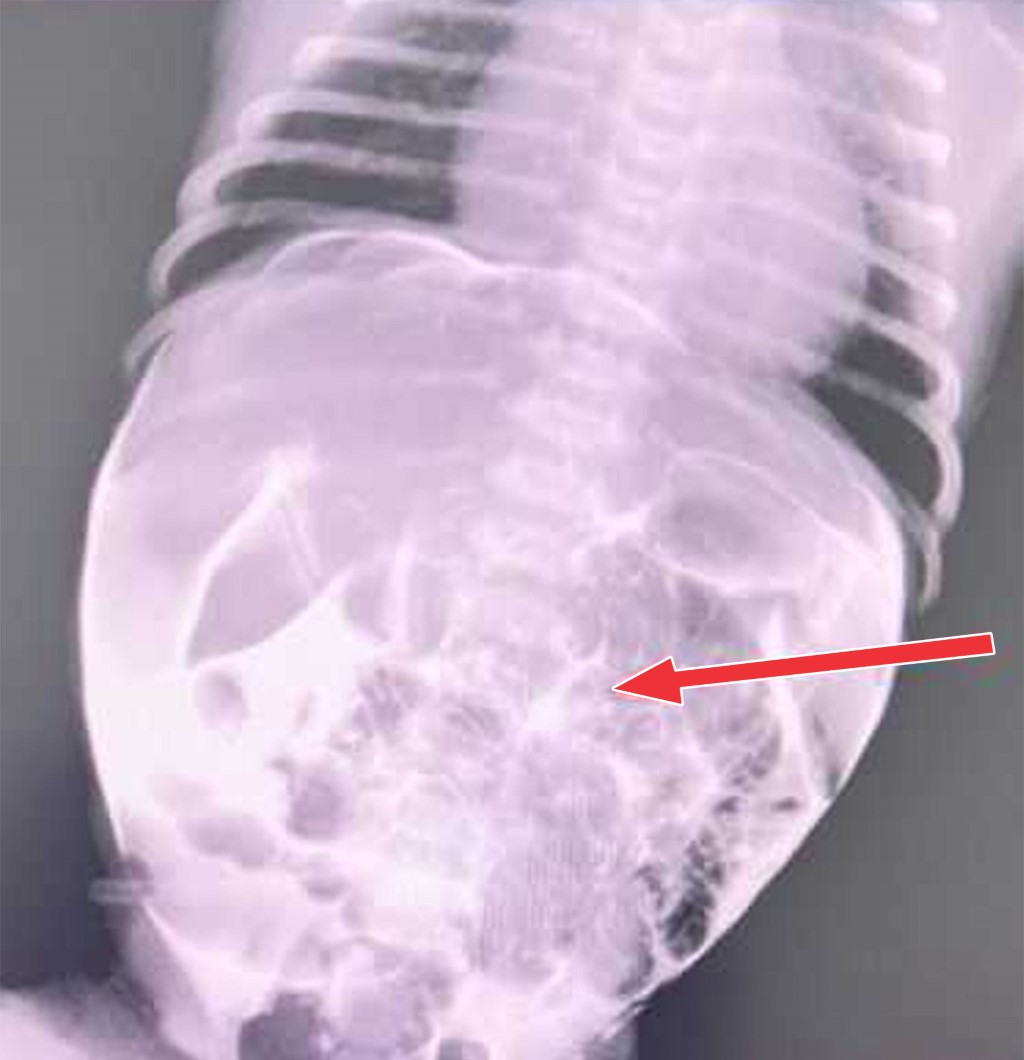

Newborn with remnant of the omphalomesenteric duct

Introduction: we present the diagnostic and therapeutic process of a newborn with a remnant of the omphalomesenteric duct. Clinical case: a male newborn was found at birth with meconium-stained umbilical cord blood. The remnant of the omphalomesenteric duct was confirmed by contrast fistulography. Surgery was performed with resection of an intestinal segment around the omphalomesenteric fistula, followed by an ileoileal end-to-end anastomosis. The patient was discharged home after 10 days due to a good recovery. Conclusion: a remnant of the omphalomesenteric duct is a rare condition; its diagnosis is based on physical examination and imaging studies. Patients have good prognosis after surgical treatment.

Figure 2